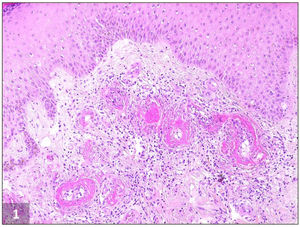

Imagen histopatológica de vasculopatía livedoide. Depósito de fibrina dentro de la pared y luz de los vasos sanguíneos dérmicos que origina engrosamiento de las paredes de los vasos y oclusión vascular debido a la trombosis. También se observan fibrosis dérmica e infiltrado linfocítico perivascular (H&E, ×100).

La vasculopatía livedoide (VL) es una enfermedad cutánea trombótica oclusiva infrecuente, que afecta principalmente a los pequeños vasos sanguíneos de las extremidades inferiores. Se trata de una situación recurrente y dolorosa, caracterizada por livedo persistente asociado a ulceraciones dolorosas recurrentes, principalmente alrededor de los maléolos, que evoluciona a lesiones cicatriciales atróficas (atrofia blanca)1–3. El diagnóstico se confirma mediante biopsia cutánea2,3, que muestra anomalías vasculares, incluyendo trombosis intraluminal, proliferación endotelial y degeneración hialina de la subíntima (fig. 1)1,2,4. Esta situación es más común en mujeres de mediana edad1–3. Su patogenia es incierta, aunque puede estar asociada a diversas coagulopatías y síndromes afines2,4,5. El inhibidor del activador de plasminógeno tipo 1 (PAI-1) es un importante inhibidor del sistema fibrinolítico, habiéndose descrito niveles elevados de PAI-1 en los pacientes con VL4,6. El tratamiento para VL es difícil, y no está bien establecido, siendo su objetivo la mejora de las lesiones cutáneas, el alivio del dolor y la prevención de la recidiva. La terapia más ampliamente prescrita es la administración de anticoagulantes (más frecuentemente como monoterapia, lográndose una respuesta favorable en el 98% de los pacientes), esteroides anabólicos (para controlar los síntomas agudos debido a su efecto antiinflamatorio, aunque también pueden aumentar la fibrinólisis y la inhibición de la coagulación), inmunoglobulinas intravenosas y antiplaquetarios, entre una serie de terapias que incluyen dipiridamol, pentoxifilina y nifedipina1,7,8. Recientemente se han utilizado, también, los nuevos anticoagulantes orales antagonistas no vitamina K (NOAC), especialmente rivaroxabán, con éxito considerable5,7–9.

El paciente número 1 fue una mujer de 42 años, que acudió a nuestra clínica con historia de pápulas purpúricas colaescentes y blandas de 14 meses de evolución en la parte baja de las piernas, que habían evolucionado a ulceraciones profundas y dolorosas, no teniendo historia clínica pasada relevante. La exploración física reveló piel moteada y úlceras perforadas rodeadas de eritema purpúrico e hiperpigmentación en ambas regiones maleolares, con eritema reticular y lívido en las piernas. Diversas úlceras habían sanado, evolucionando a cicatrices esteladas atróficas (fig. 2A). La biopsia cutánea fue compatible con VL (fig. 1). Se detectó homocigosidad 4G/4G del promotor PAI-1 en la secuenciación de ADN. Se prescribieron aspirina y prednisolona oral, observándose una mejoría leve. Se rebajó gradualmente la dosis de prednisolona (hasta 5mg/día), manteniéndose la dosis estándar de aspirina como terapia de mantenimiento. Sin embargo, se documentó una nueva recidiva en 4 meses. Se introdujo una dosis de edoxabán (15mg/día), con resolución clínica completa en 5 meses. A los 7 meses de seguimiento su situación era buena.